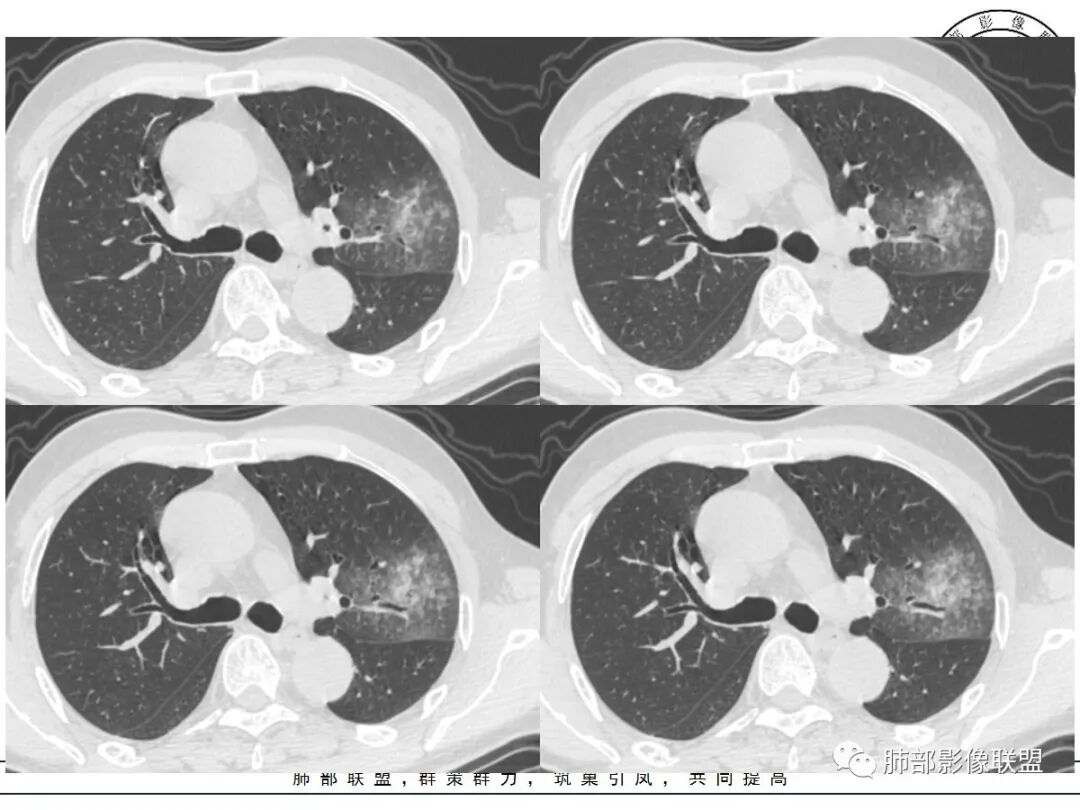

这三个月后的

发了后面这个,就不用纠结了,直接秒了。

大雄:

我只是要告诉大家,不是二元,就是肿瘤,没有什么感染,磨玻璃都没消失。

反思,恶性膨隆,远端空洞,强化坏死不均,里面血管似乎也是增粗,边界不清,似乎有侵犯。坏死还是边界不清。

1、团片状,实行密度区外观整体圆顿,位于上叶尖后段与下舌段区间。局部膨隆,但未见分叶,肿瘤多见。

2、偏心空腔病灶,气腔略呈新月形,壁不规则,腔内结节相对密实,明显强化且不均,支持新生物而非曲菌球等。炎性空洞多有强化环。

3、病变强化较明显,其内隐约显示多发小斑片状无强化灶,可疑边界不清小灶坏死区。病灶内血管影浅淡、模糊不规则。

4、支气管改变:上舌段支气管远段延入部分稍示僵硬。尖后段见分支支气管阻塞,恶性多见。

5、周围磨玻璃,3个月后逐渐转为密实,应符合当初附壁生长为主,且逐渐向实体成分转换。

6、病变长轴平行且受限于胸膜,外围大内带小,符合外朝内发展病变。“腔内结节状明显强化”加之支气管改变有力支持新生物诊断。如此大范围边界不清的磨玻璃影让人浮想联翩。如此大范围病灶,肺门纵隔未见肿大淋巴结也让人意外。